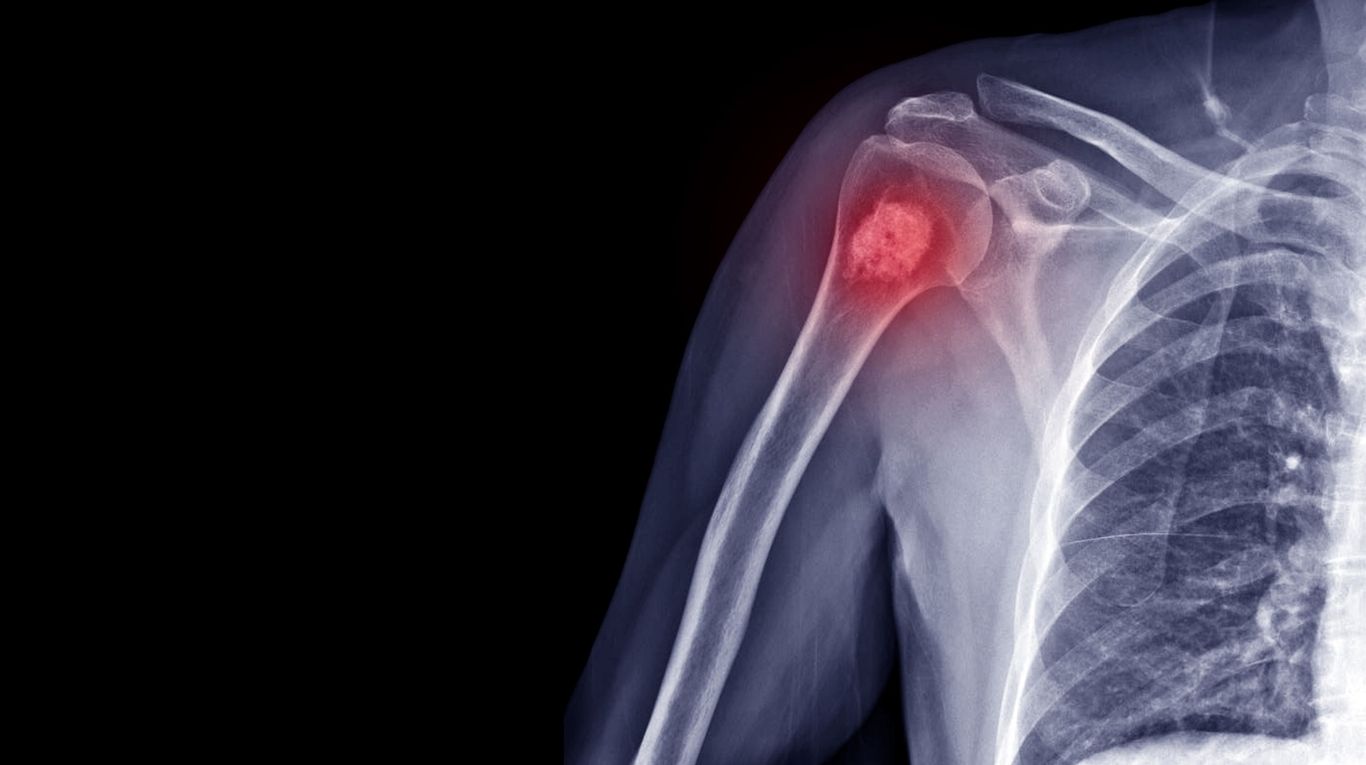

ओस्टियोसारकोमा एक तरह का हड्डी से जुड़ा कैंसर है। इसको समझने के लिए जरूरी है कि आप पहले यह जान लें कि कैंसर क्या होता है? यह एक खतरनाक और जानलेवा बीमारी है। इसकी अलग-अलग स्टेजेस हो सकते हैं। यह बीमारी शरीर के किसी भी हिस्से में हो सकती है। यह तब शुरू होता है, जब बॉडी सेल्स नियंत्रण से बाहर होने लगती हैं। शरीर के लगभग किसी भी हिस्से की कोशिकाएं कैंसर बन सकती हैं और फिर यह शरीर के किसी भी हिस्से में फैल सकती हैं। ओस्टियोसारकोमा जिसको ओस्टोजेनिक सार्कोमा भी कहते हैं यह कैंसर का सबसे आम प्रकार है, जो हड्डियों में शुरू होता है। कैंसर सेल्स हड्डियों में नए सेल्स बनाती हैं, लेकिन ये हेल्दी सेल्स की तरह मजबूत नहीं हाती हैं। यह बीमारी ज्यादातर बच्चों, किशोरों और युवाओं में होती है। टीनेजर्स इस बीमारी की चपेट में सबसे ज्यादा आते हैं लेकिन, इसका मतलब यह नहीं है कि वयस्कों को इस बीमारी का रिस्क नहीं होता है। बहरहाल, यह बात हम सभी जानते हैं कि यह एक घातक बीमारी है। कई लोगों के मन में यह सवाल उठ सकता है कि क्या इस बीमारी से बचा जा सकता है? यानी क्या यह बीमारी पूरी तरह ठीक हो सकती है? तो आइए जानते हैं इस आर्टिकल के जरिए।

ओस्टियोसारकोमा